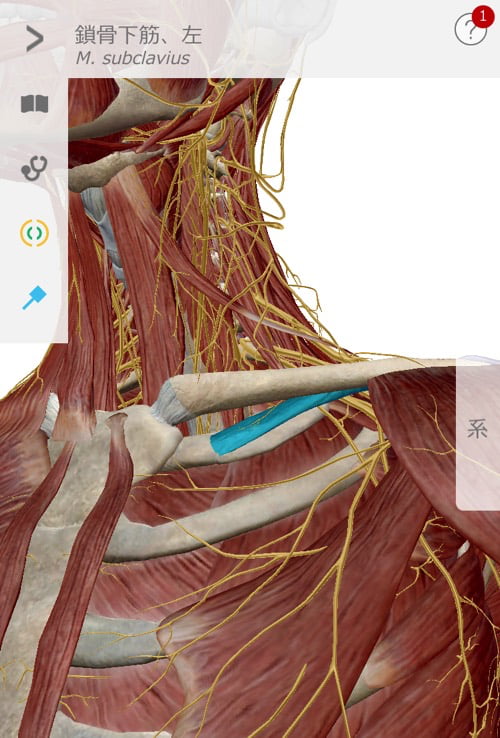

そして四十肩に大きく関連している鎖骨周りを調整。